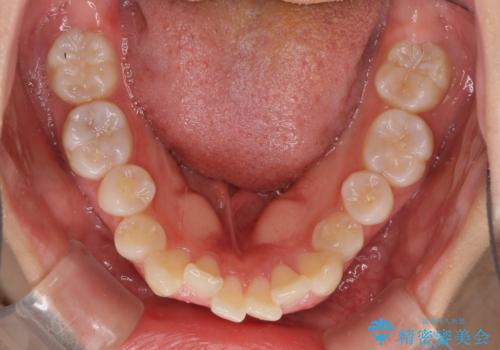

- 出っ歯とデコボコを気にして来院された患者様です。

口元の突出感を改善するため、上下左右第一小臼歯4本の抜歯を行い、ワイヤー装置による矯正治療を行うこととしました。